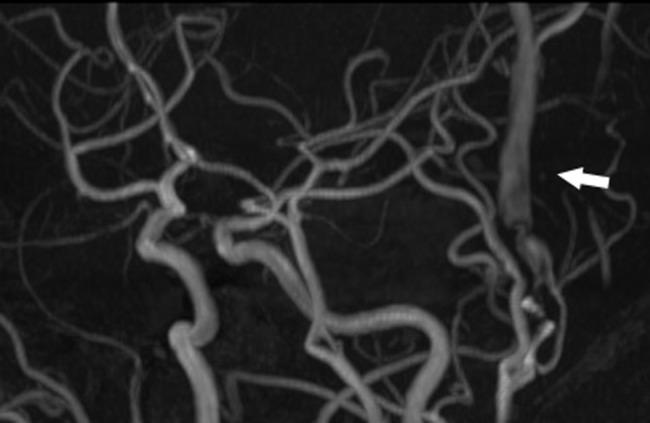

Traumatic arteriovenous fistula (AVF) of the superficial temporal artery (STA) is rare. We report a case of surgically treated, histopathologically confirmed traumatic AVF of the STA. A 24-year-old male was admitted to our hospital after a traffic accident. Computed tomography scan on admission showed an acute epidural hematoma on the right surface of frontal lobe, which was emergently treated by surgical evacuation. One month later, he was aware of pulsatile tinnitus around the left ear. Digital subtraction angiogram showed an AVF, mainly fed by the left STA. After total removal of the fistula, his tinnitus immediately disappeared. Histopathological examination demonstrated that the artery was connected to the vein through the thin-walled vessels lacking internal elastic lamina and muscularized media, suggesting that the connecting vessels were newly formed.

颞浅动脉创伤性动静脉瘘(AVF)较为罕见。我们报告一例经手术治疗、组织病理学确诊的颞浅动脉创伤性AVF病例。一名24岁男性在交通事故后入院。入院时的计算机断层扫描显示右额叶表面急性硬膜外血肿,遂紧急行手术清除。1个月后,他感觉到左耳周围有搏动性耳鸣。数字减影血管造影显示一个AVF,主要由左颞浅动脉供血。瘘管完全切除后,他的耳鸣立即消失。组织病理学检查表明,动脉通过缺乏内弹性膜和肌化中膜的薄壁血管与静脉相连,提示这些连接血管是新形成的。